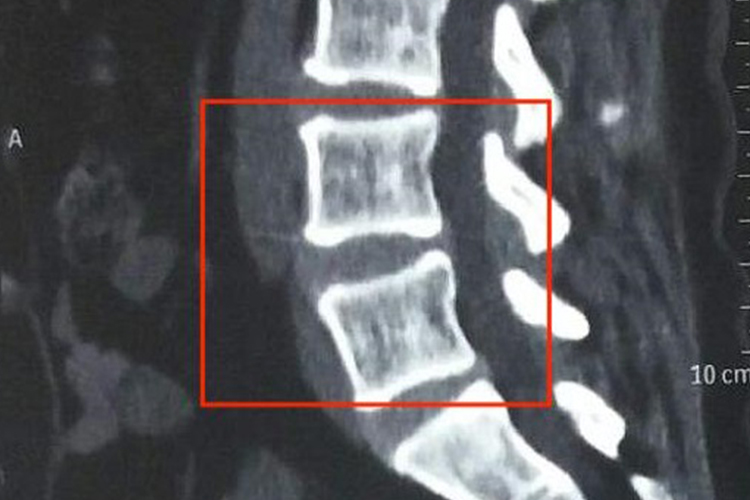

脊椎L4L5即第四、第五腰椎,正常CT表现为在椎弓根层面上,由椎体后缘、椎弓根、椎板和棘突围成一个完整的骨环,L4L5的椎体较粗壮,横断面呈肾形,上下关节突粗大,椎管前后径下限为11.5mm,横径下限为16mm,侧隐窝宽度下限为3mm,在椎间盘及其上下面,椎体与椎板不相连,其间有脊神经和血管通过。

脊椎L4L5CT异常表现为椎管扩大,椎弓根变平或凹陷,椎弓根间距增宽和椎体后缘凹陷,椎间孔扩大伴边缘骨质硬化,硬膜囊前或前外侧缘受压,可能见于脊椎及附近肿瘤、腰椎间盘突出症等疾病。